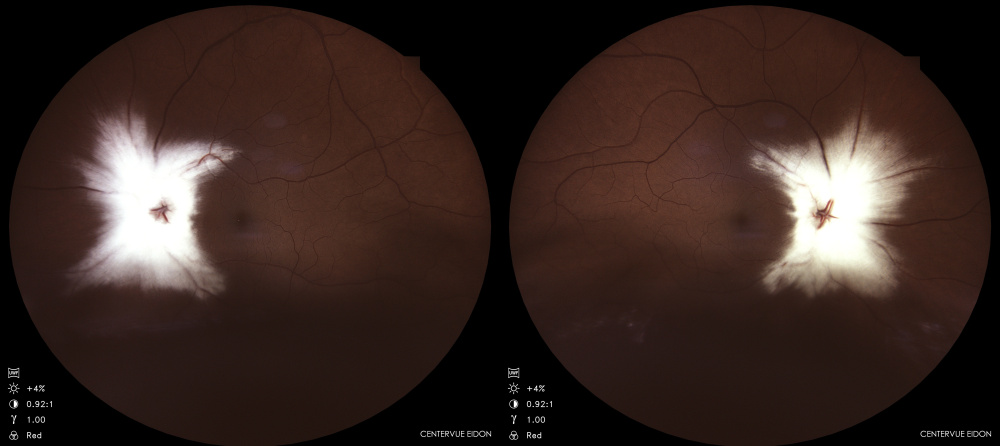

Título: Mielinização Bilateral Extensa da Camada de Fibras Nervosas Retinianas

Autor: Bernardo Monteiro

Coautores:

Instituição: ULS Santa Maria

Descrição: Retinografias de uma doente de 47 anos com mielinização bilateral exuberante da camada de fibras nervosas, um achado incidental com impacto visual e relevância clínica.